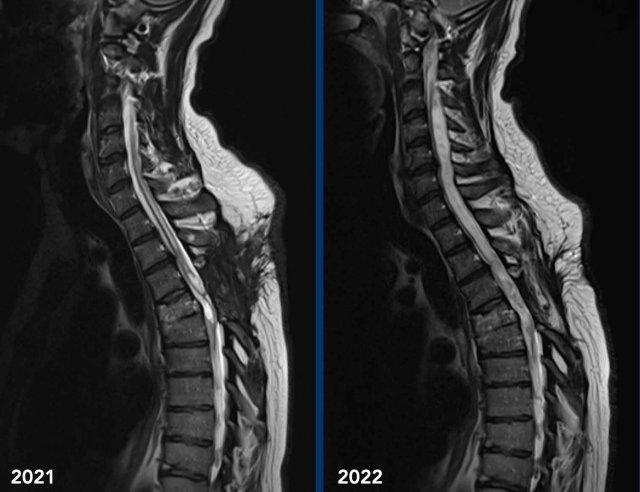

Những hình ảnh này của một người đàn ông 45 tuổi đã bị chấn thương tủy sống do chấn thương ở mức T4-5 vài năm trước.

Hiện tại bệnh nhân có biểu hiện đau tiến triển ở hai chân với giảm phản xạ ở cả hai tay và hai chân cùng với hội chứng Horner hai bên.

Hình ảnh

Hình ảnh cộng hưởng từ cột sống cổ-ngực chuỗi xung T2 TSE theo mặt phẳng đứng dọc năm 2021 cho thấy mất chiều cao thân đốt sống T4 kèm theo tổn thương tủy sống và nhuyễn tủy dạng nang tại vị trí này cùng với hình ảnh rỗng tủy-não thất tủy xung quanh.

Hình ảnh cộng hưởng từ cột sống cổ-ngực chuỗi xung T2W theo mặt phẳng đứng dọc năm 2022 cho thấy hình ảnh rỗng tủy-não thất tủy tiến triển.

Continue with the next images…

Hội chứng Horner có thể được giải thích bởi tình trạng rỗng tủy tiến triển ở mức cổ gây gián đoạn các tế bào thần kinh bậc một của đường dẫn truyền giao cảm nhãn cầu.